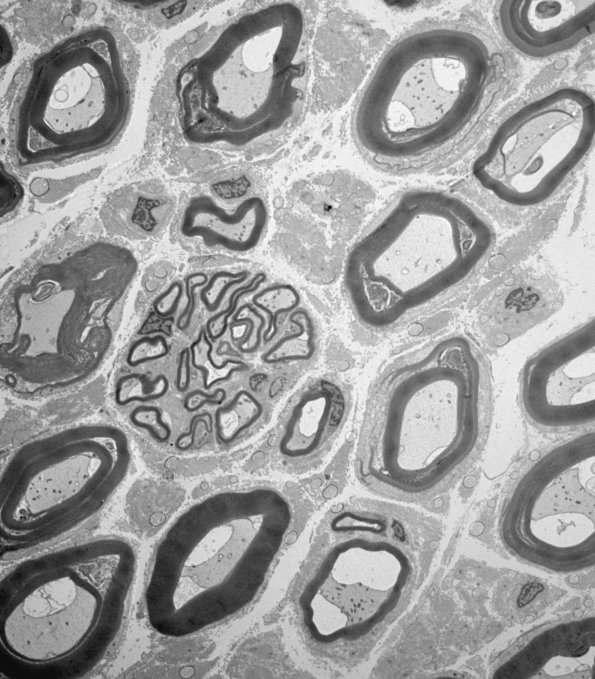

This low magnification electron micrograph shows numerous large myelinated axons and a cluster of thinly myelinated small normal appearing axons. (Electron micrographs)